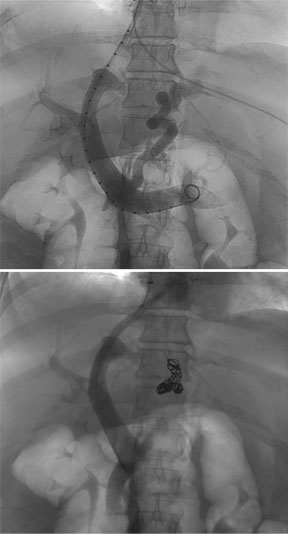

Left gonadal venogram demonstrates a large left varicocele and two parallel collateral veins that were embolized to complete vascular stasis using hot iodinated contrast and gelfoam. The left testicular pain and swelling have remained resolved for 6 years.